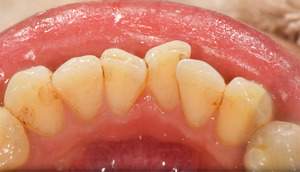

歯石除去

治療前

治療後

| 年齢 | 40歳・男性 |

| 主訴 | 歯石をとりたい |

| 治療内容 | 歯石除去 |

| 治療期間 | 30分 |

| 費用 | 約2,000円 |

| リスク・副作用 | ・歯ぐきの炎症が強いと歯石を取る際に出血することがあります。 ・処置後に歯がしみることがあります。 ・歯と歯の間に隙間ができるので、息が漏れ発音しにくいと感じることがあります。 ・歯ぐきの炎症が軽減すると歯ぐきが引き締まり、歯が長く見えることがあります。 |